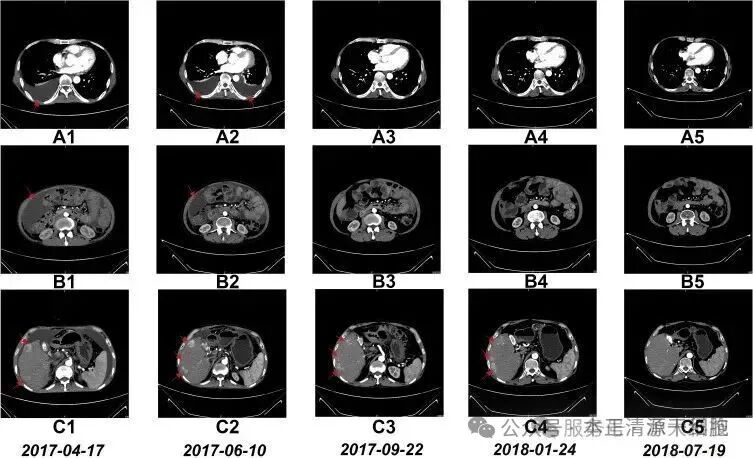

经NK细胞免疫治疗后,所有患者的客观缓解率为14.3%,疾病控制率为71.4%;从短期临床疗效上看,接受疗程数多的患者疗效稍好于接受疗程数少的患者;且治疗前后,患者均无不良反应出现,充分说明了NK细胞免疫疗法的安全性、有效性。

这位晚期肝癌患者,正在用真实的生命经验,印证着NK细胞疗法的临床价值,更揭示了免疫治疗从“对抗肿瘤”到“系统重建”的范式转变。他的故事象征着医学对“绝症”定义的颠覆——当免疫系统被重新激活,癌症或许不再是生命的终点,而是一场可管理的慢性战役。随着技术迭代与临床证据积累,NK细胞疗法正从边缘探索迈向主流舞台,为无数患者点亮“向死而生”的希望之光,改写癌症治疗史的“生命奇迹” 。